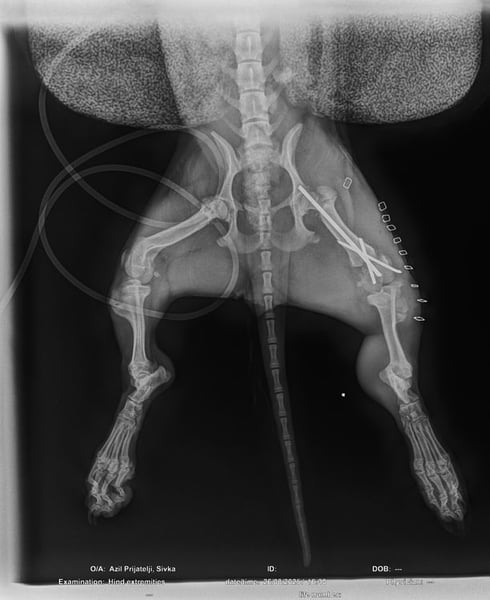

Bemerkungen: Ilse wurde von einem Auto angefahren und erlitt dabei einen Beinbruch. Weitere Informationen über den Beinbruch sind im nachfolgenden Text enthalten.

Dies hat sich dann vermutlich Ilse abgeschaut und gedacht, wenn das die Junghunde können dann kann das ein kleines und zartes Welpenmädchen auch. Leider keine gute Idee von Ilse, dann sie wurde von einem Auto angefahren und brach sich dabei einen Knochen am Hinterbein.

Ihr Frauchen bat nun unser kroatisches Partnertierheim um Hilfe bei er Operation. Die Tierheimleiterin stimmte dieser Sache zu, allerdings nur unter der Voraussetzung, dass Ilse dann im Tierheim bleiben durfte und Ilse sich dann eine neue Familie suchen darf. Ferner stellten wir die Bedingung, dass sich die zuständigen Behörden den Tierbestand der Frau anschauen und nötige Impfungen und Kastrationen durchführen darf. Die Frau stimmte diesen Bedingungen zu. Ilse wurde operiert und durfte bei der Tierheimleitung im Wohnhaus einziehen und hat sich dort zu einer richtigen kleinen Schönheit entwickelt.

Die Operation verlief erfolgreich, allerdings schont Ilse ihr Bein zur Zeit noch. Da Ilse aber noch sehr jung ist, wird dies vermutlich recht schnell heilen und Ilse wird ihr Bein auch wieder normal belasten. Die unten beigefügten Videos machen Mut und Freude.

Für den Muskelaufbau wird Ilse vermutlich etwas Physiotherapie benötigen.